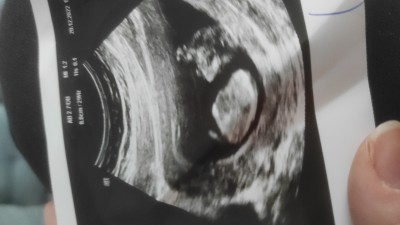

Cinsiyet anlayan varmı acaba cok merak ediyorum doktor göremedi emin olamadı tahminlerinizi bekliyorum :)

Gebelik haftası 14+5